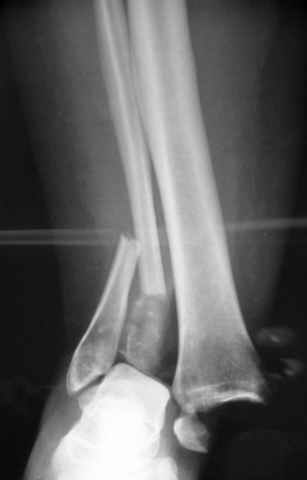

Pilon fracture:

ET> ЕЧ При подобных переломах фиксация малоберцовой кости обеспечивает

ET> низведение латерального тибиального фрагмента - появляется ориентир для

-Появляется ориентир и остов, на чем можно строить восстановление, почему сперва малоберцовую, впервые обьяснили и описали (Pylon type and Ankle fractures) в середине 50х Rienau и Gay.

Восстановливая длину и ротацию малоберцовой кости, затем относительно легче произвести реставрацию остальных элементов перелома дистального эпиметафиза болшеберцовой кости.

конец малоберцевой кости, к нему прикрепляется латеральный суставной фрагмент дистального эпиметафиза большеберцовой кости (как на снимке)

и таранная кость, которые при репозиции малоберцовой кости репонируются автоматически.

Дистракция в аппарате или на вытяжение результат - лигаментотаксис, посмотреть бы, как сегодня расположены отломки.